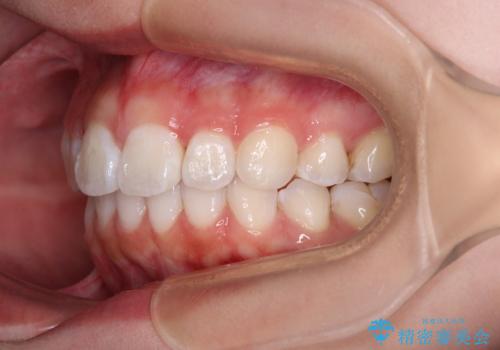

- 上下前歯の叢生を気にして来院された患者様です。

インビザラインでの治療を希望されていて、デコボコの程度が中等度であり、安価なパッケージにて対応可能と判断されたため、インビザライン・モデレートを用いて矯正治療を行うこととしました。